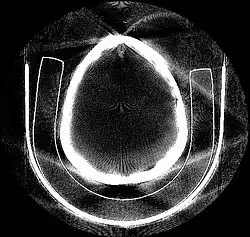

Tomographic reconstruction is a type of multidimensional inverse problem where the challenge is to yield an estimate of a specific system from a finite number of projections. The mathematical basis for tomographic imaging was laid down by Johann Radon. A notable example of applications is the reconstruction of computed tomography (CT) where cross-sectional images of patients are obtained in non-invasive manner. Recent developments have seen the Radon transform and its inverse used for tasks related to realistic object insertion required for testing and evaluating computed tomography use in airport security.[1]

Deep learning methods are widely applied to image reconstruction nowadays and have achieved impressive results in various image reconstruction tasks, including low-dose denoising, sparse-view reconstruction, limited angle tomography and metal artifact reduction. An excellent overview can be found in the special issue [5] of IEEE Transaction on Medical Imaging. One group of deep learning reconstruction algorithms apply post-processing neural networks to achieve image-to-image reconstruction, where input images are reconstructed by conventional reconstruction methods. Artifact reduction using the U-Net in limited angle tomography is such an example application.[6] However, incorrect structures may occur in an image reconstructed by such a completely data-driven method,[7] as displayed in the figure. Therefore, integration of known operators into the architecture design of neural networks appears beneficial, as described in the concept of precision learning.[8] For example, direct image reconstruction from projection data can be learnt from the framework of filtered back-projection.[9] Another example is to build neural networks by unrolling iterative reconstruction algorithms.[10] Except for precision learning, using conventional reconstruction methods with deep learning reconstruction prior [11] is also an alternative approach to improve the image quality of deep learning reconstruction.